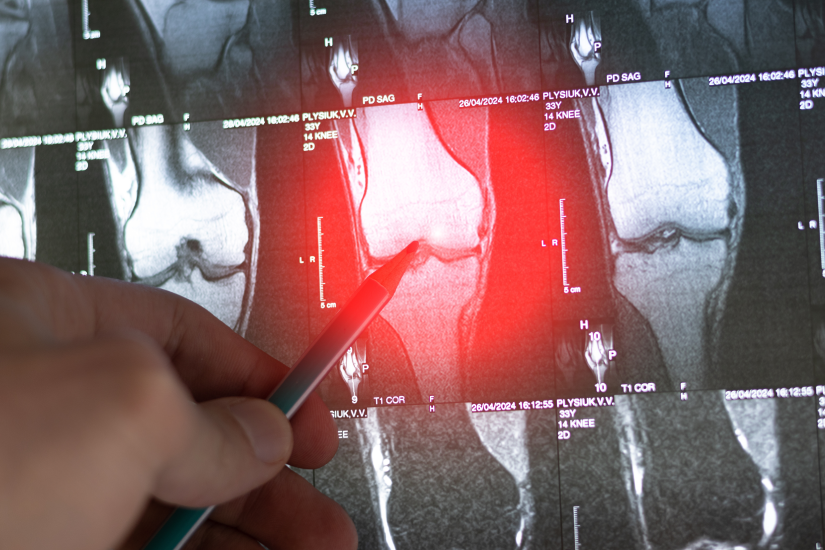

- Diagnosticul se bazează pe o combinație de teste imagistice (radiografii, RMN, CT) și este confirmat printr-o biopsie osoasă.

- Pasul 2: Efectuează investigațiile inițiale: Medicul va recomanda probabil o radiografie osoasă a zonei dureroase. Aceasta este adesea prima investigație care poate ridica suspiciunea unei tumori.

- Pasul 3: Solicită o evaluare specializată: Dacă radiografia arată o anomalie, vei fi trimis către un specialist în ortopedie oncologică sau un centru specializat. Aici se vor efectua investigații imagistice avansate (RMN, CT, eventual PET-CT) pentru a caracteriza leziunea și a evalua extinderea bolii.